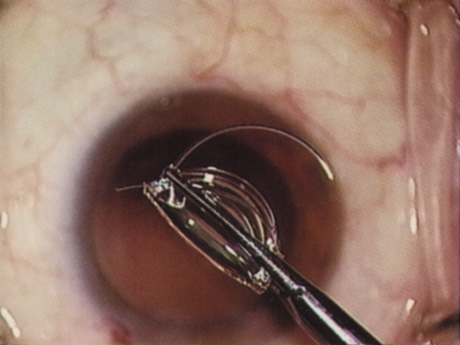

A mature cataract precludes visualization of the fundus. A B-scan ultrasonographic examination provides a real-time, two-dimensional (2D), cross-sectional image of the globe along the marked axis of the probe (Fig. 3). Cataracts are more common in patients with chronic retinal detachment, prior trauma, or intraocular tumors; therefore, a B-scan study is helpful in excluding structural posterior segment pathology before surgery on a mature cataract. Although a negative result to B-scan evaluation is reassuring, the surgeon should remember that it does not predict postoperative visual outcome. The B-scan can be thought of as a picture of Cincinnati from an airplane; the office buildings may all be standing, but you cannot tell whether the people in them are working.